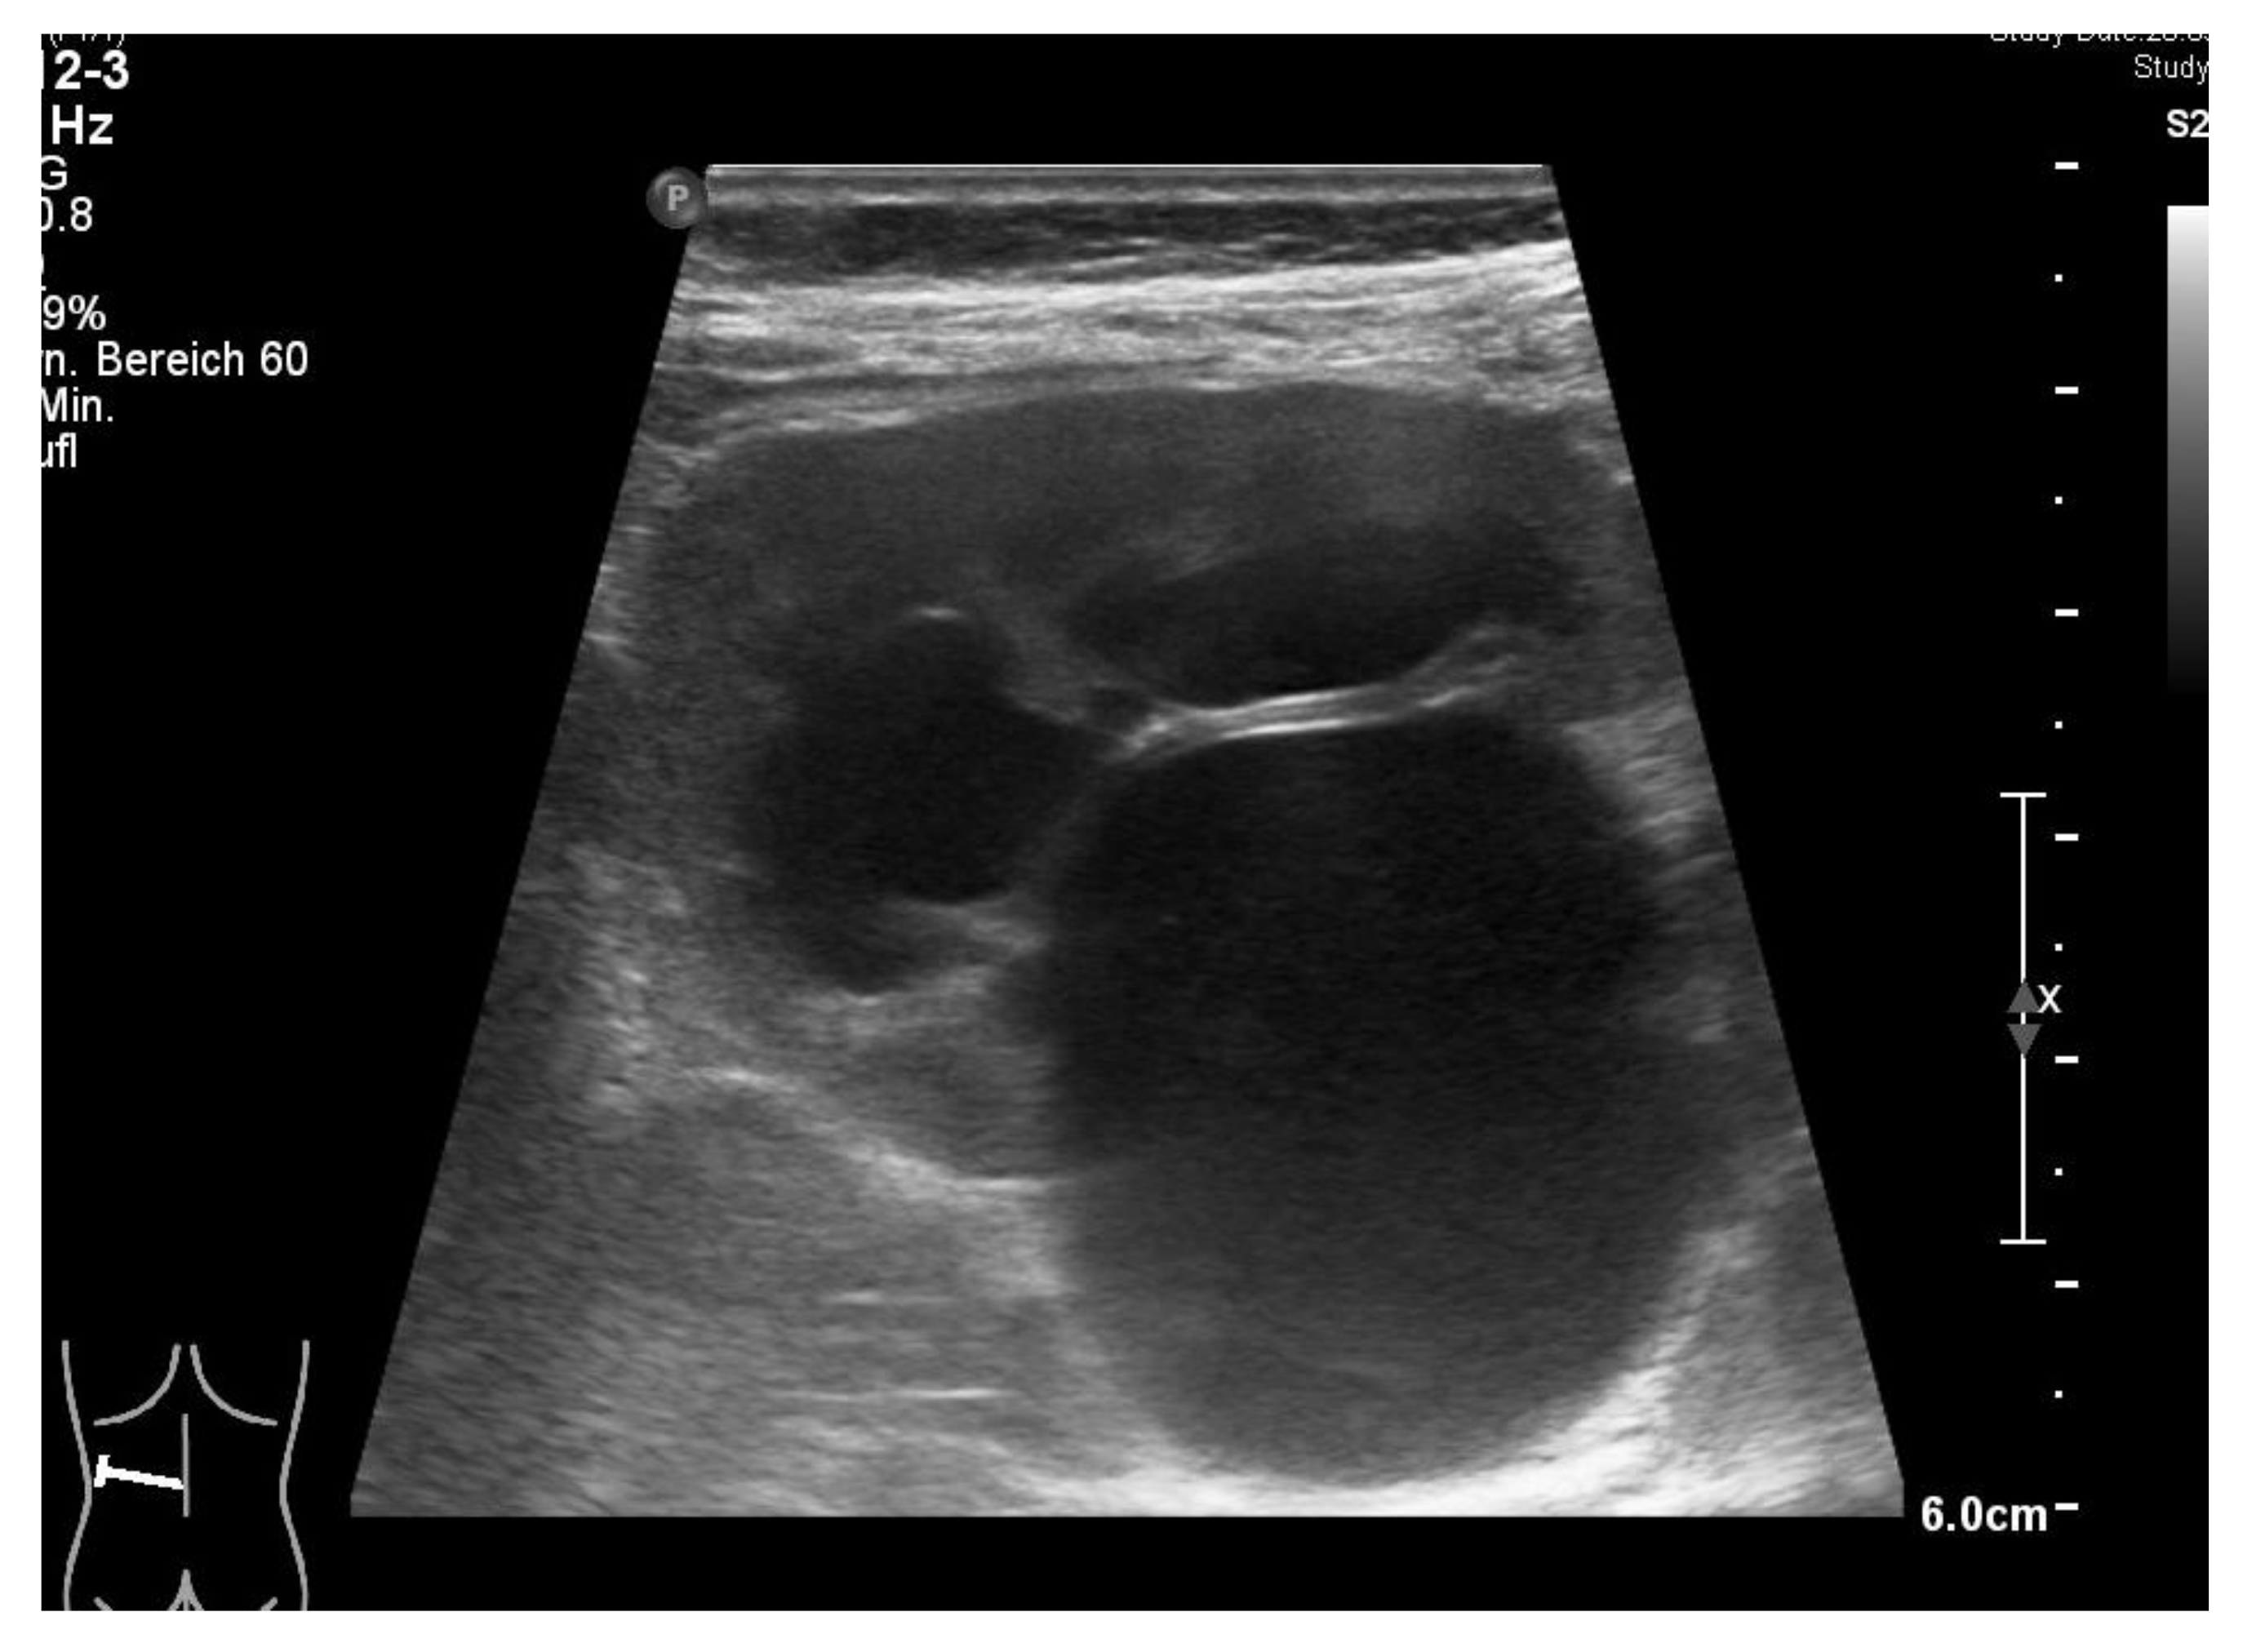

2.2. Patient

We present the case of a girl with a first proven febrile urinary tract infection at the age of 15 months. Her history revealed several previous episodes of fever of unknown origin, some treated with antibiotics, but no additional comorbidity. On assessment, she had a raised c-reactive protein (CRP, maximum 133 mg/L), a normal serum creatinine (0.37 mg/dL), and an isolated left-sided third grade hydronephrosis, suggestive of ureteropelvic junction stenosis with a 2.8 cm pelvic dilatation (Figure 1). Catheter urine showed >1000 leucocytes per high power field, and Escherichia coli was isolated (105/mL). She responded well to parenteral cefuroxime and was discharged after five days with oral prophylactic trimethoprim.

3. Results

Postoperatively, the patient was transferred to the regular pediatric ward. On POD-2, she had one event of intermittent fever (38.9 °C); antibiotic therapy was switched from cefuroxim to cefotaxime, according to the antibiogram with E. coli in the urine test. On POD-4, the urinary catheter was removed, after the ultrasound control (Figure 6) had revealed a regression of the pyelon dilatation and a ureteral catheter correctly placed. On POD-6, the abdominal drain was removed. On POD-7, the patient was dismissed with normal kidney function and a normal CRP (2.7 mg/L). Histology revealed a chronic fibrosis of the resected left pyelon and of the left ureter.

Figure 1. Ultrasound test of 1.5-year-old girl (19 May 2020) presenting with recurrent febrile urinary tract infections shows dilatation of the pyelon and hydronephrosis of the left kidney (courtesy of Dr. A. Longin, Klinikum Esslingen).

Figure 6. Ultrasound test after left-sided robotic pyeloplasty before dismission shows normal kidney without dilatation of the pyelon (courtesy of Dr. A. Longin, Klinikum Esslingen).